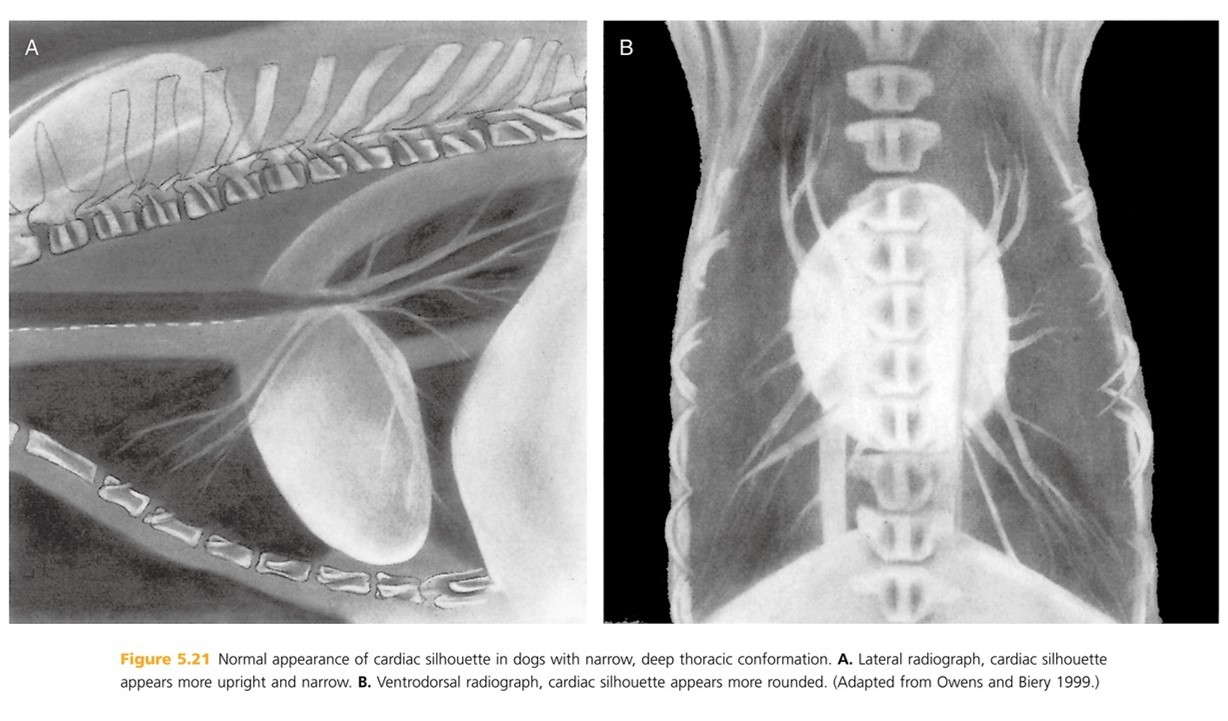

The heart is obliquely positioned in thoracic cavity:

Lateral radiograph?

Ventrodorsal radiograph?

Lateral rad- long axis is approximately 45 degrees to perpendicular

Ventrodorsal rad- long axis is approximately 30 degrees to spine